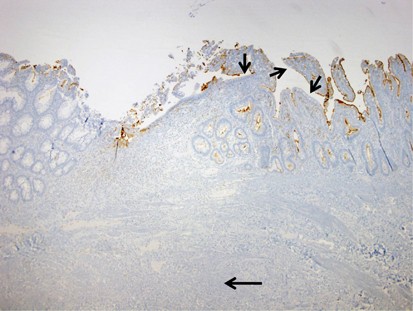

In total, 103 specimens were retrieved and stained with CD10 (35 colonic and 68 enteric). All 35 colons (100%) were negative for CD10, regardless of clinical setting (five normal, six colostomies, five colonic anastomoses, six ulcerative colitis, five diversion colitis, and eight Crohn's colitis), and whether or not they were actively inflamed. All normal small intestines (6/6; 100%) and normal ileocecal valves (3/3; 100%) had uniformly positive CD10 staining of the enteric mucosa (Figure 1). Surgically altered small intestinal specimens from patients without inflammatory bowel disease had patchy loss of CD10 staining in 5/25 cases (20%). Specifically, there were 12 ileostomies, 6 enteroenteric anastomoses, and 7 enterocolic anastomoses, all of which came from patients without inflammatory bowel disease. Of these, one ileostomy (8%), one enteroenteric anastomosis (17%), and three enterocolic anastomoses (43%) had patchy staining, all with loss of CD10 expression on ≤10% of the epithelium (Figure 2). The ileostomy and the enteroenteric anastomosis with loss of staining both had active inflammation, while one of the three enterocolic anastomoses was actively inflamed.

CD10 staining of an enterocolic anastomosis section. The mural scar of the anastomosis can be seen in the bottom portion of the photomicrograph (arrow). The colonic mucosa (left) is uniformly negative for CD10. Most of the enteric mucosa (right) is positive, but there are areas close to the anastomotic junction that are negative (small arrows).